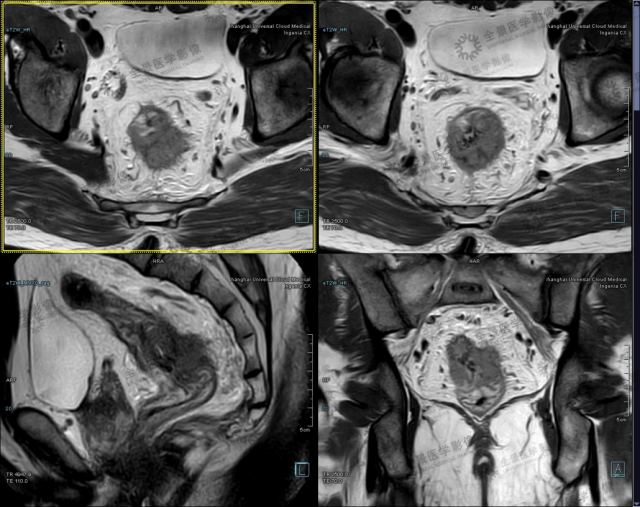

病例 2 男性,43 岁,大便带血 2 月,2020-07-11 行肠镜示:直肠癌,距肛门 11 cm 至 8 cm 见不规则隆起肿物。病理:管状绒毛状腺瘤癌变。

直肠癌 T3 期,小视野 T2WI 可见肿块突破固有肌层,周围模糊,伴壁外结节影。